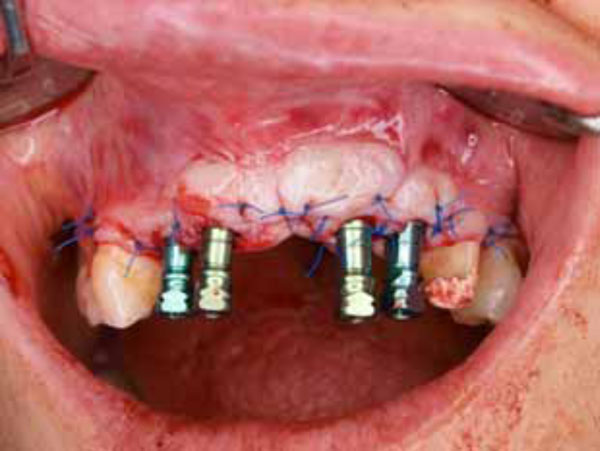

Implant surgery and the papilla regeneration technique (second surgery). A full-thickness flap was elevated, and simultaneously, an immediate implantation was performed in the right central tooth area. Semilunar bevel incisions were made, recreating a scalloped shape similar to that of tissues around natural teeth (The rotation of the pedicles made it possible to close the space between the abutments).

Suturing of the flap.

regeneration was performed. A full-thickness flap was elevated and reflected labially. The healing abutments held the flap in place. Semilunar bevel incisions were made, recreating a scalloped shape similar to that of tissues around natural teeth. The tissue was rotated towards the palate to create a papilla between the implant and the tooth. The flap pedicles filled the interimplant space. Sutures (5.0-trofilen monofilament; polyvinylidene fluoride) were used to secure the tissues. This technique was done not only around implants placed four months previously, but also immediately after for the additional implants placed that day (Fig. 4, 5).